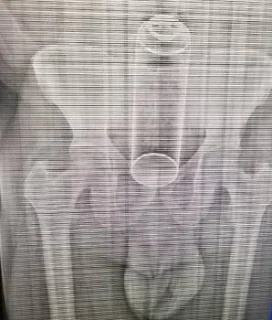

Un hombre fue intervenido quirúrgicamente luego de que se le

alojara un frasco de insecticida en el recto mientras sostenía relaciones

sexuales con su pareja.

El hombre, de 40 años, llegó al hospital Moscoso Puello con el objeto alojado en el recto, según informó el relacionista del centro asistencial, Hanobi Delgado.

Según versiones, el paciente buscaba placer sexual mientras sostenía relaciones con su esposa, quien asegura que ella le introdujo el frasco por petición del caballero.

Tras la operación, que duró unas dos horas, el paciente fue puesto en observación. El cuerpo médico informó que el hombre se encuentra estable, fuera de peligro.